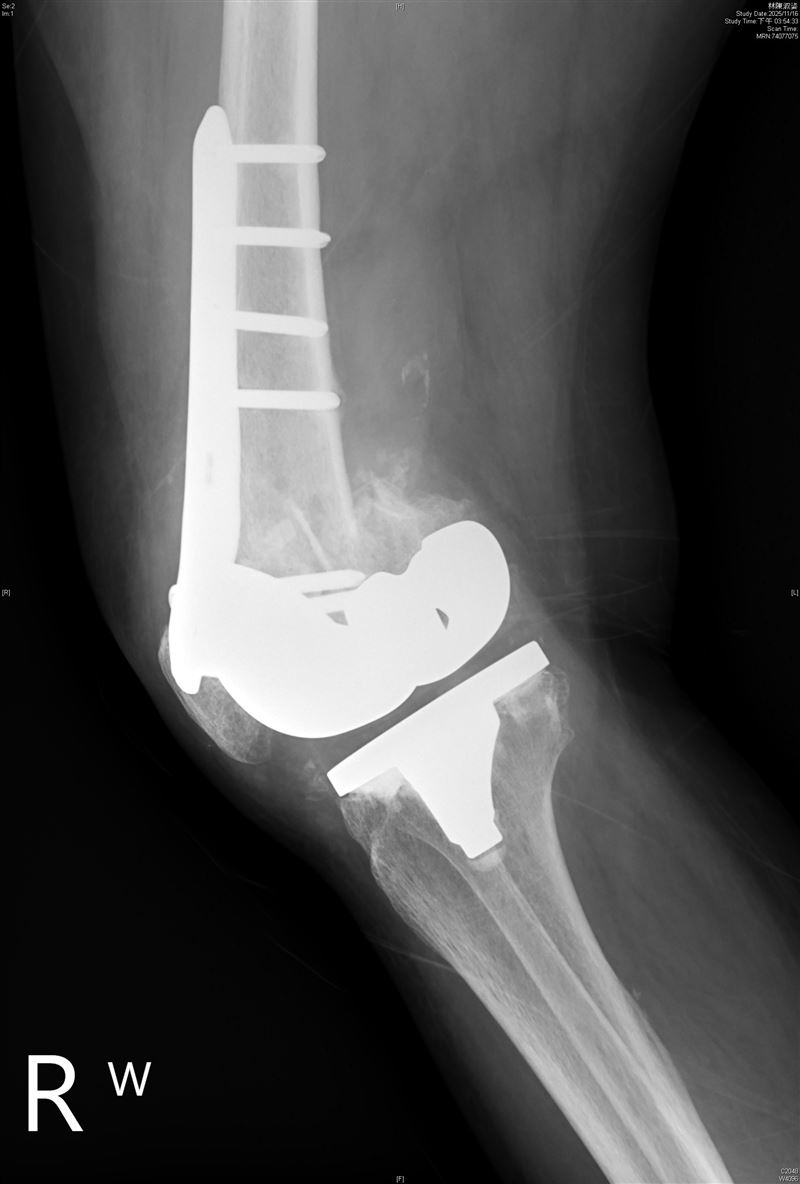

收治個案的北市聯醫陽明院區骨科主治醫師王大翊表示,考慮到高齡長者長期臥床將面臨肌肉流失、肺部感染、褥瘡等致命併發症,醫療團隊決定採取「人工膝關節再置換手術」,利用特殊設計的人工關節取代壞死骨組織。所幸手術極為順利,許奶奶術後第二天即可下床,經過三週密集復健,如今已能重返社區,享受逛街與聚會生活。